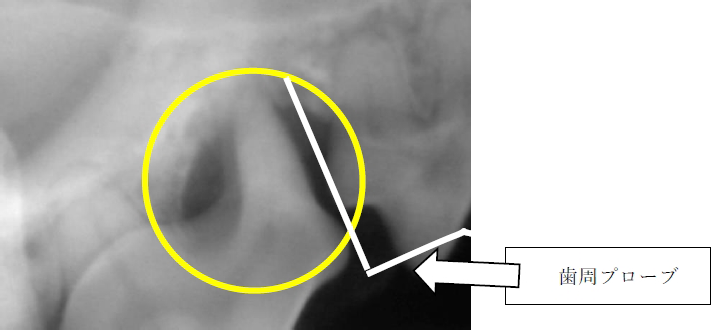

見た目は歯肉炎もなくキレイでしたが、歯周プローブを用いると一箇所だけ歯周プローブが入り込む場所がありました。その場所の歯科レントゲン検査を実施したところ、下記の写真のようになりました。

|

第4前臼歯の近心根の周囲の骨は歯周病により溶けてしまいました。歯根のまわりがどのようになっているかの評価に関しては、 CT 検査を実施するか、このような歯科レントゲン検査を実施しないと判断ができません。